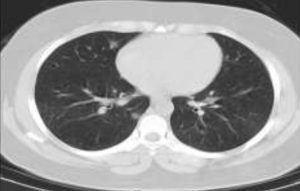

یافته های سی تی اسکن در بیماران مبتلا به کووید – 19

با توجه به اهمیت درگیری ریه در بیماران مبتلا به کرونا و نقشی که سیتی اسکن در تشخیص و انتخاب درمان بیماران دارد، این مطالعه با حجم نمونه بزرگ بر روی نتایج سیتی اسکن ریه بیماران مبتلا به کووید-19 انجام شد.